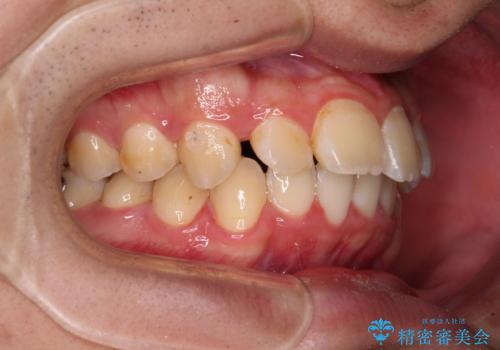

下顎の歯列は、奥歯が前方に傾斜し、前歯が上顎の歯の付け根に食い込むように内側に傾斜していました。

また、左右の犬歯の位置関係は上顎歯列が前方に位置する咬み合わせとなっており、インビザライン単体で治療するよりは、ワイヤー装置や補助装置を併用した方がより良い仕上がりになることが期待されました。

来院時は学生であったので、補助装置により上顎臼歯を後方に移動させ、下顎歯列はワイヤー装置による傾斜を改善させ、就職のタイミングでインビザラインにて仕上げていくこととしました。